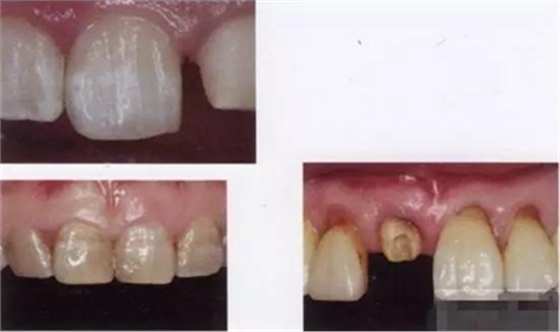

【主訴】上前牙充填物脫落兩個(gè)月

【病史】上前牙一年前行根管治療,充填物部分脫落,自覺(jué)影響美觀,從不敢笑,要求先行樹(shù)脂修復(fù)。(年齡:14歲)

【檢查】12,11,21,22,均行玻璃離子充填,各牙不同程度部分充填物脫落,探(—),叩(—),冷刺激無(wú)反應(yīng),無(wú)松動(dòng),牙齦顏色粉紅,質(zhì)地堅(jiān)實(shí)而有彈性,點(diǎn)彩正常,牙結(jié)石(—);牙髓活力測(cè)試無(wú)反應(yīng)。

【診斷】12,11,21,22牙體缺損

【治療計(jì)劃】

1.美容評(píng)估,取模體外制備舌側(cè)背板

2.制作纖維樁

3.復(fù)合樹(shù)脂充填